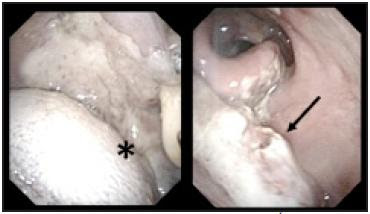

Linfoma T/NK extraganglionar tipo nasal: Caso clínico

El linfoma T/NK extraganglionar tipo nasal es un linfoma extraganglionar, habitualmente expresa el fenotipo NK y VEB positivo. Cursa ocasionando necrosis y angioinvasión afectando de manera preferente estructuras mediofaciales. Característicamente es muy agresivo. Presentamos un caso con una sobrevida de siete meses a partir de los primeros síntomas y realizamos revisión de la literatura.

Extranodal NK/T-cell lymphoma nasal type, is an extranodal lymphoma, usually with an NK-cell phenotype and EBV possitive. It causes necrosis and angioinvasion, and it is most commonly presenting in the midfacial area. Characteristically it is very aggressive. A case with survival of seven months from the first symptoms is reported and a review of the literature is made.